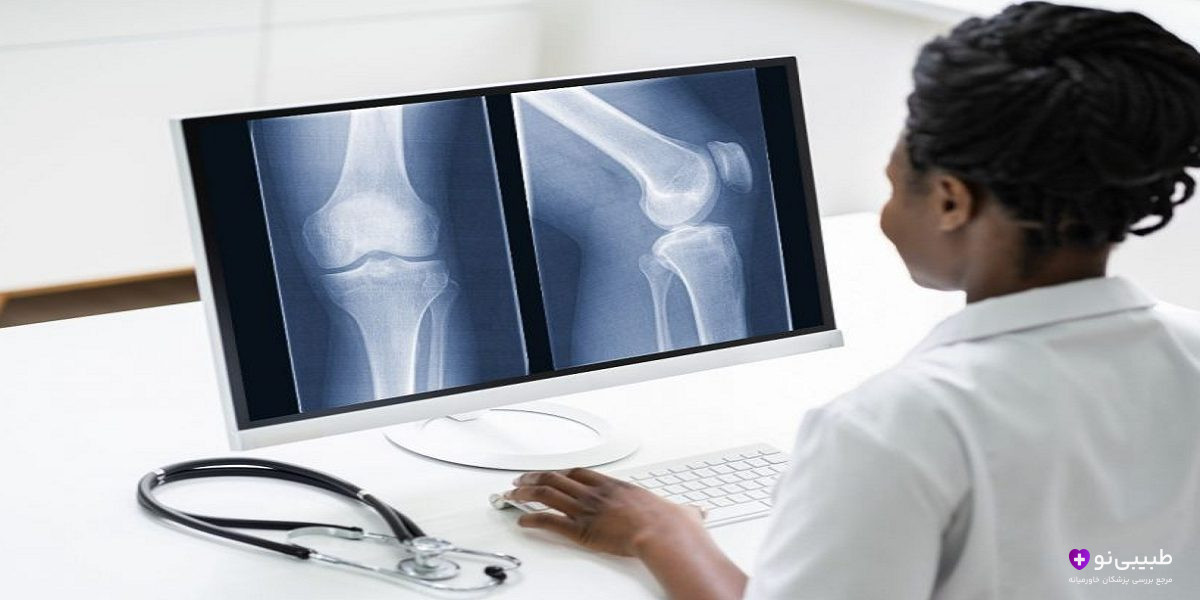

تشکیل کالوس در رادیوگرافی

یکی از مهمترین شاخصهای علمی برای تایید بهبود استخوان شکسته تشکیل کالوس (Callus) است. این شاخص معرف توده استخوانی موقتی در اطراف ناحیه شکستگی میباشد. در واقع کالوس مانند پلی بین دو سر شکسته استخوان عمل میکند. تصاویر رادیوگرافی بعد از شکستگی چند ویژگی دارند:

- مشاهده واضح خط شکستگی استخوان

- ایجاد سایهای سفید و نامنظم در اطراف محل شکستگی طی چند هفته

- مشاهده ساختار استخوانی مستحکم بعد از گذشت ۶ الی ۱۲ هفته

این تصاویر درک بهتری از وضعیت بهبود استخوان طی چند هفته ایجاد میکنند.

رادیوگرافی و ام آر آی

تصویربرداری پزشکی نقش محوری و مهمی در تایید بهبود استخوان شکسته دارد. ارزیابی کالوس و محو شدن خط شکستگی توسط رادیوگرافی (X-ray) بسیار مرسوم است. البته در موارد پیچیده پزشکان تصویربرداری با MRI را پیشنهاد میدهند.